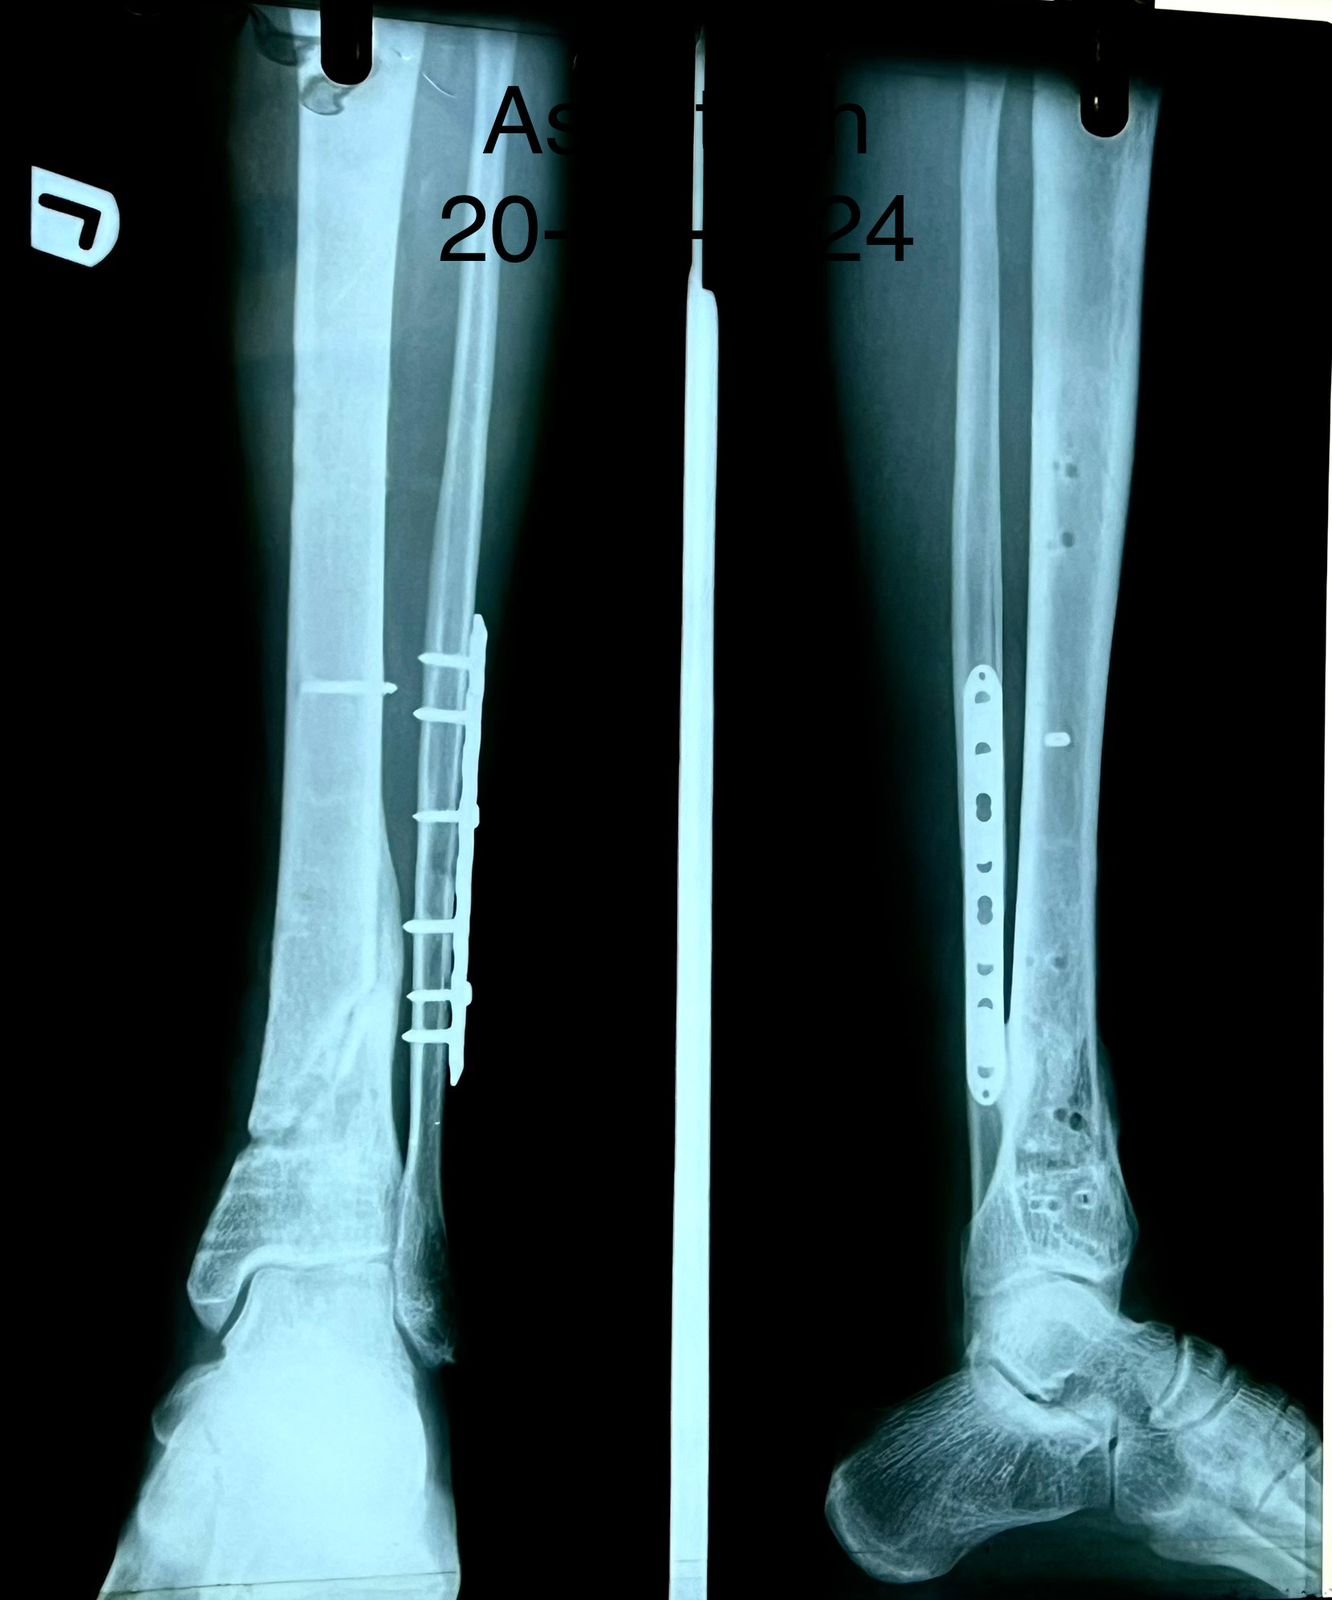

Pre op & postop X-ray compound fracture lower tibia

& fibula | Heal fracture pre & postop | Clavicle